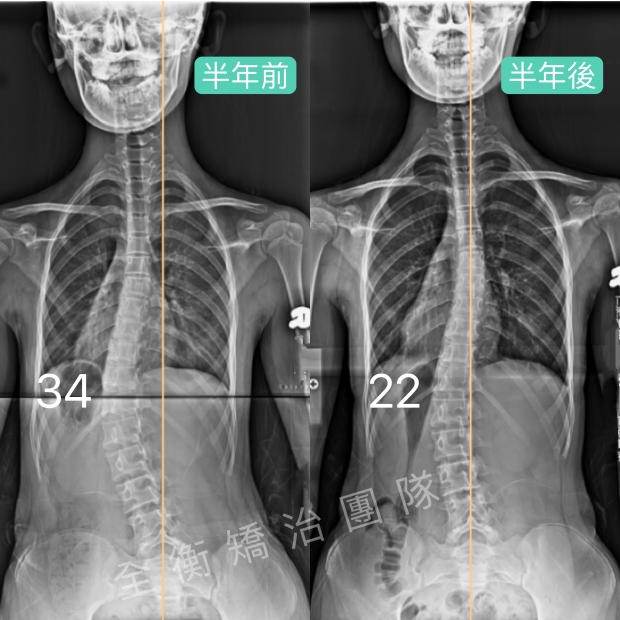

14歲側彎女生努力不懈、持之以恆,追求進步14歲側彎女生努力不懈、持之以恆,追求進步

14歲的女孩,胸腰大彎34°,旋轉15°,骨齡3,柔軟度不佳,

歷經長達兩年多的專業側彎復健運動+穿戴德國施羅斯背架矯治,

體態回正,度數從34°減少至19°,進步44%,旋轉也從15°減少到3° -